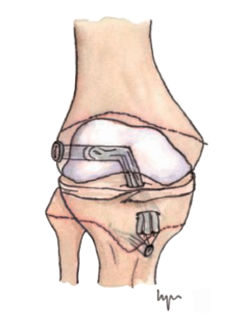

Otra de las técnicas de ahorro fisario es la llamada all epiphyseal. La primera de estas técnicas fue descrita por Anderson(13)(Figura 4) y está indicada en pacientes en estadio de Tanner I, II o III. Se realiza evitando la invasión de la fisis por parte de los túneles, utilizando injerto cuadrifascicular de isquiotibiales, que son estabilizados en el fémur mediante un sistema de tenosuspensión cortical y en la tibia con un tornillo interferencial distal a la fisis (Figura 5). Los resultados en un grupo de 12 pacientes fueron buenos, pero refieren que la técnica es compleja y demandante para un cirujano no experto en rodilla. Esta técnica minimiza el daño fisario, es anatómica y reproduce la isométrica(71). Se ha descrito la aparición de una deformidad angular relacionada con una epifisiodesis secundaria por sobretensionado de la plastia. En la actualidad, se han descrito multitud de modificaciones de esta técnica(15,72,73,74)(Figura 6).

Figura 6. Esquema de las modificaciones técnicas de la técnica todo epifisaria. A: técnica All-inside de Arthrex®; B: OrthoPediatrics®.

Lawrence et al.(72) realizan un túnel femoral paralelo a la fisis y otro túnel tibial central, ambos asistidos por tomografía computerizada intraoperatoria y reconstrucción 3D para comprobar que no se invaden las fisis. La fijación del autoinjerto de 4 fascículos se realiza con tornillos interferenciales.

McCarthy et al.(15) modificaron la técnica anterior utilizando los mismos principios. Sin embargo, el autoinjerto se fija con un sistema de suspensión cortical en ambos lados, femoral y tibial. De esta forma, evitan la colocación de un tornillo interferencial en hueso esponjoso epifisario y facilitan la reproducción anatómica de la huella del LCA nativa.